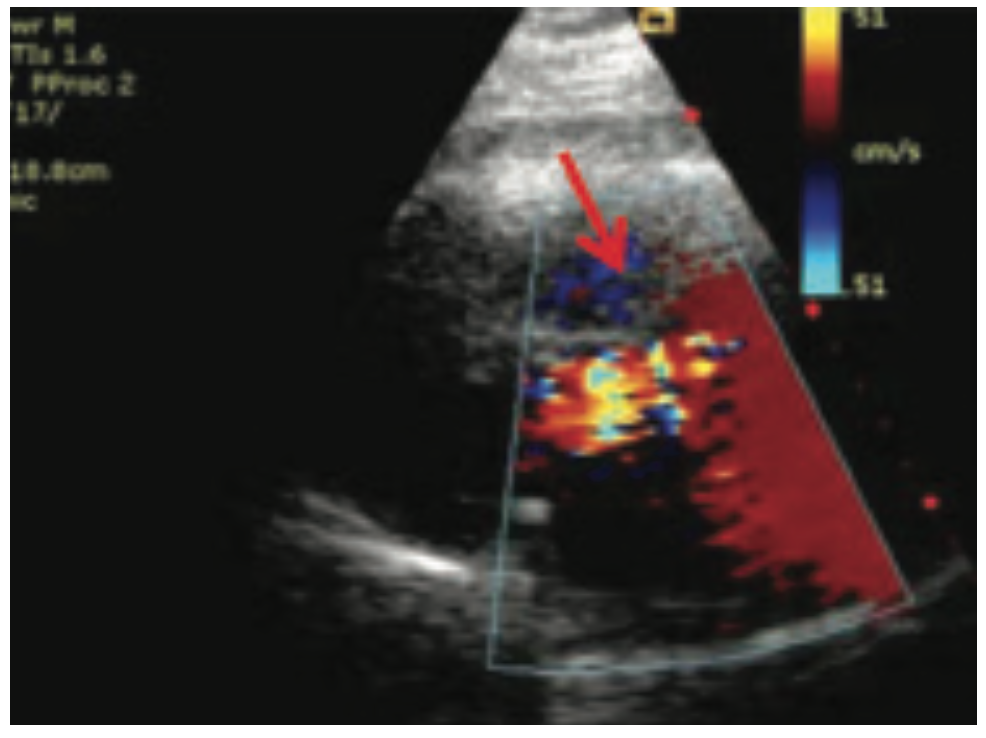

She was widowed, lived alone, and quit smoking 4 years ago, with a 40 pack-year smoking history. Her family history was non-contributory. She had noticed some dyspnea on exertion during routine chores such as mowing the lawn and carrying laundry upstairs, which she attributed to deconditioning. She was otherwise asymptomatic, even during her episode of supraventricular tachycardia (SVT) during her recent colonoscopy. During her TTE, the technologist notified the cardiologist of a 9-centimeter ascending aortic aneurysm, effacing the sinotubular junction with dilated sinuses of Valsalva. The TTE also demonstrated moderate aortic regurgitation. There was no evidence of vegetation or aortic dissection, or pericardial effusion. The patient was admitted to the University Hospital from the office for further management. A computed tomography scan of the chest with contrast was done in the emergency department to further define the aneurysm. Cardiac catheterization was performed the following day, revealing normal coronaries, normal left ventricular systolic function, and a 9-centimeter ascending aortic aneurysm. She underwent urgent cardiothoracic surgery. The surgeon repaired her aortic root with a Dacron patch and replaced her aortic valve with a bioprosthetic pericardial aortic valve. The patient had an otherwise unremarkable post-operative course, primarily consisting of blood pressure control. She was discharged with surgical follow-up within 1 week and cardiology follow-up in 2 weeks.